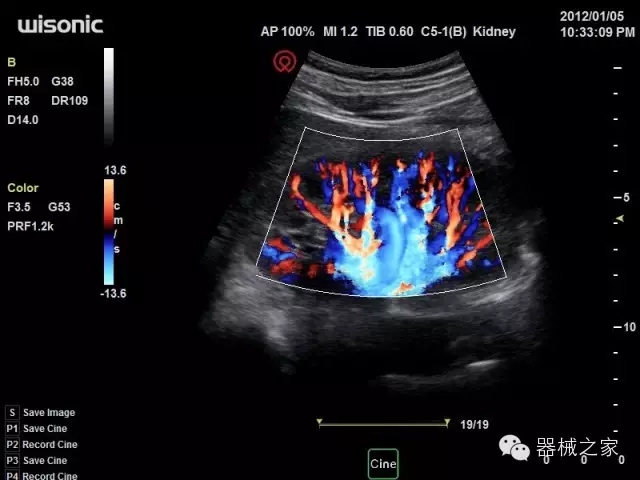

經(jīng)典產(chǎn)品:四葉草

臨床圖片賞析

產(chǎn)品特點(diǎn)

·全球目前唯一一款配備主機(jī)雙探頭接口,整機(jī)重量(含電池)在5公斤以內(nèi)的便攜式彩超;

·一款互聯(lián)網(wǎng)彩超,只要有手機(jī)信號的地方就可以非常方便地實(shí)現(xiàn)遠(yuǎn)程會診和病案調(diào)?。?/span>

·鎂鋁合金外殼,堅(jiān)固可靠耐用;

·獨(dú)有的HoloTM PW 實(shí)時3取樣門PW成像技術(shù),精確進(jìn)行血管診斷;

·一鍵優(yōu)化B、Color、PW,Auto Doppler自動識別血管位置、偏轉(zhuǎn)角度等,提高工作效率;

·30°超廣角精細(xì)偏轉(zhuǎn)成像技術(shù),更優(yōu)異的頻譜圖像;

·W+智能搜索引擎,快速尋找圖像;

·SSD、USB3.0保障開機(jī)快,導(dǎo)出圖像更快,減少等待時間;

·WIFI、網(wǎng)口、3G,多重聯(lián)網(wǎng)方式,全天候保障云端備份,不再擔(dān)心圖像丟失;